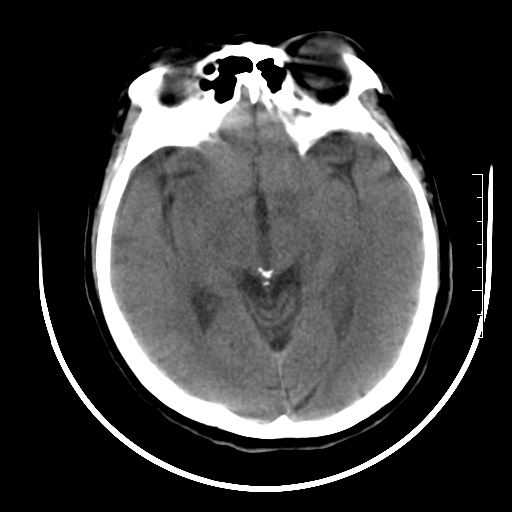

标题: CT27880:f、55y,头痛。 [打印本页]

标题: CT27880:f、55y,头痛。

考虑左侧顶部镰旁脑膜瘤;建议行ct增强扫描检查。

考虑左侧顶部镰旁脑膜瘤,建议行ct增强扫描检查。

考虑左侧顶部镰旁脑膜瘤;建议行ct增强扫描检查

大脑镰旁脑膜瘤可能,建议增强或mri

左侧顶部镰旁脑膜瘤,增强